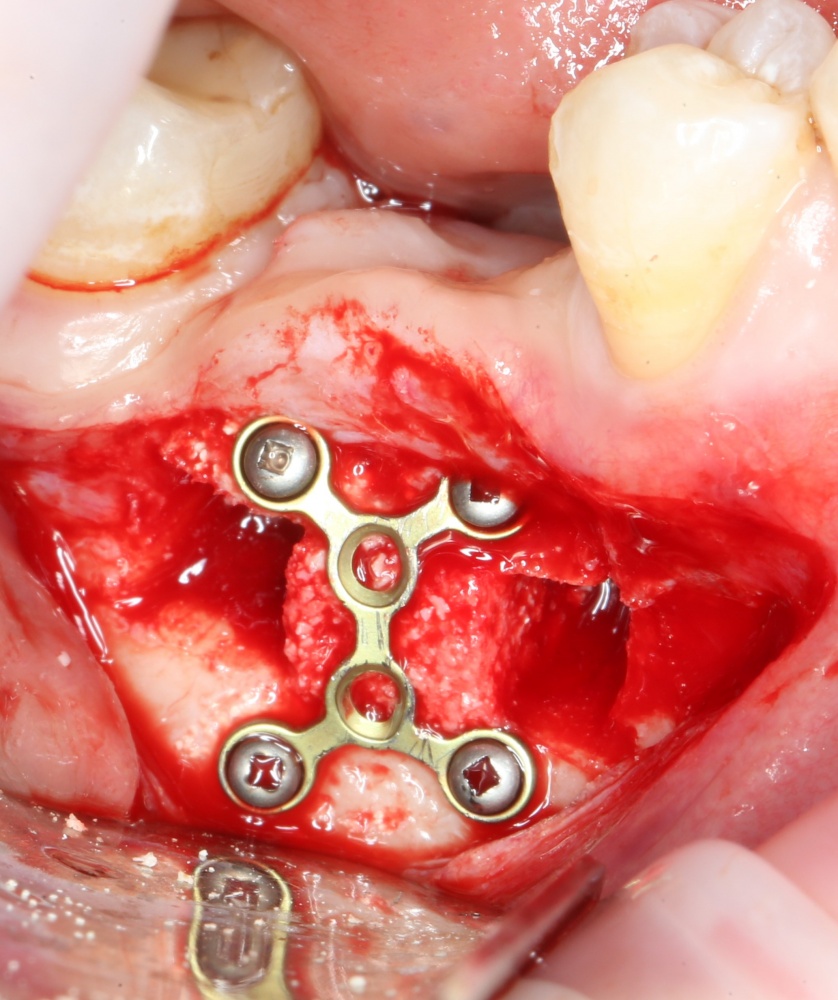

При горизонтальной остеотомии, на мой взгляд, удобнее использовать минипластины. Как я уже отмечал выше, в практике мы используем X- и H-образные минипластины под винты размером 0.9х4мм. Количество металла в разных условиях может быть разным — всё зависит от того, на каком этапе достигается полная неподвижность перемещенного костного фрагмента.

7. Заполнение образовавшегося пространства графтом.

В какой момент это делать? Наверное, если Вы используете графт в виде твердого блока, то, мне кажется. разумнее сначала уложить графт, затем проводить фиксацию перемещенного костного фрагмента винтами или минипластинами: